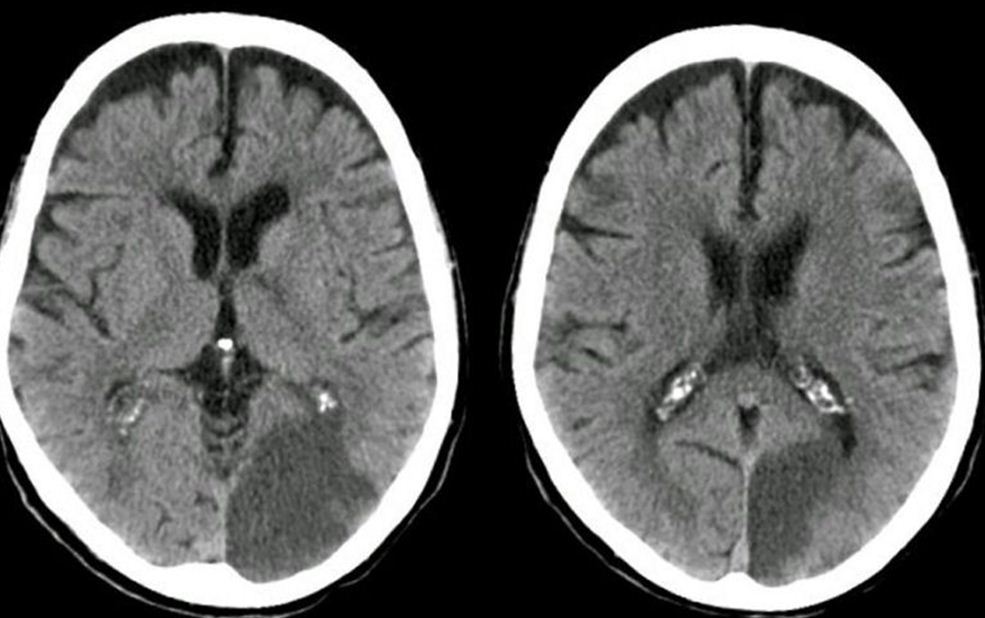

Stroke Syndrome:

In a right handed individual…

Transient hemiparesis Dysarthria Abulia or agitation inattentive, abulia, forgetful, agitation, psychosis

Bilateral caudate infarcts - from ACA distribution